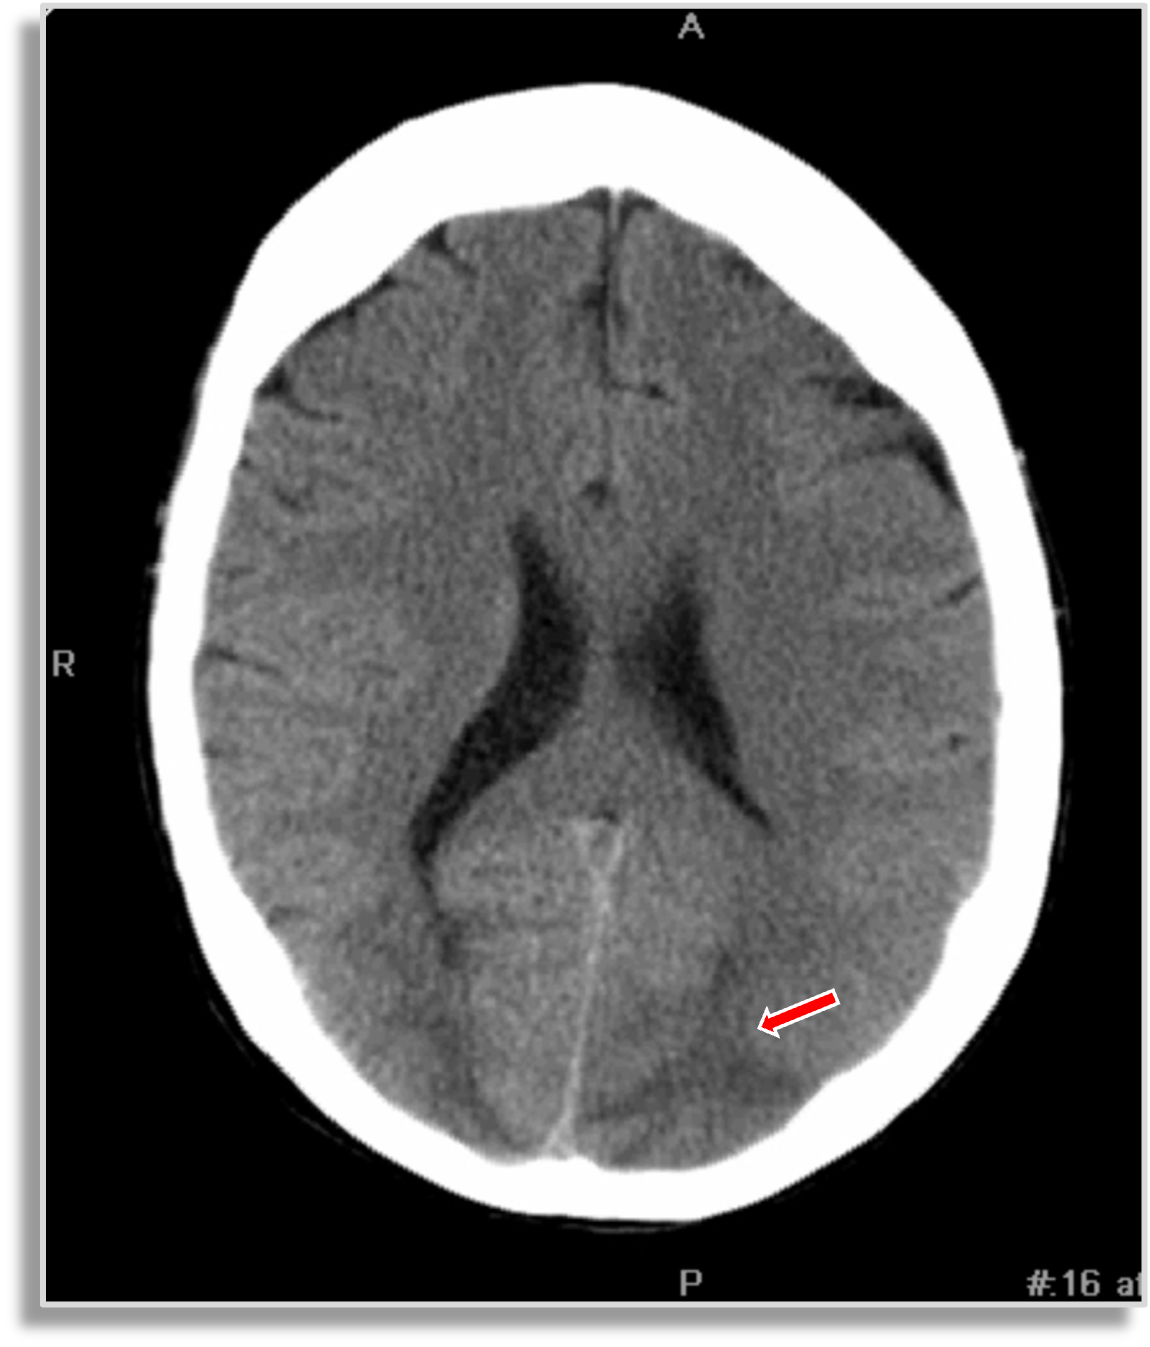

Red arrow: occipital density.

A 38-year-old female presents with hypertension and visual disturbance. What is the diagnosis?